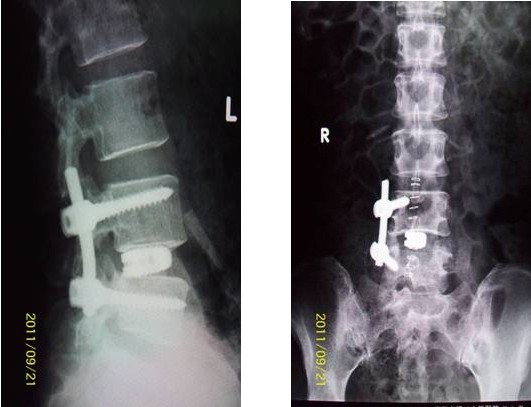

病例匯報(bào)1老年女性患者,因“反復(fù)腰腿痛10年、加重伴左下肢麻痛2月”之主訴入院,術(shù)前左下肢肌力3+級(jí),淺感覺減退。術(shù)后腰腿疼緩解,肌力及感覺恢復(fù)正常。(1、圖2)

術(shù)后腰椎X線提示單側(cè)釘棒系統(tǒng)固定穩(wěn)妥,椎間隙高度恢復(fù)正常,融合良好。(圖2